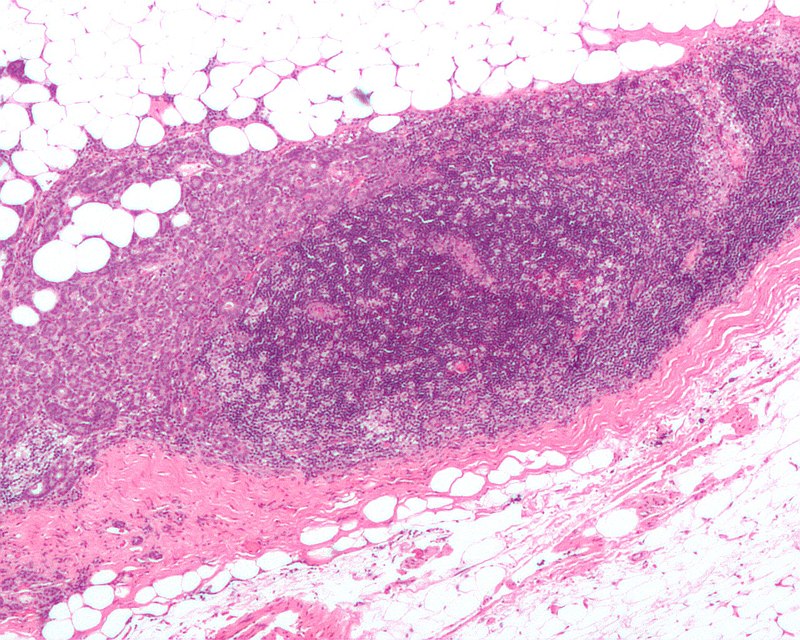

The histology of Phyllodes tumor shows leaf-like projections.

Phyllodes tumor is a tumor with an overgrowth of the fibrous component that resembles a fibroadenoma.

Phyllodes Tumor